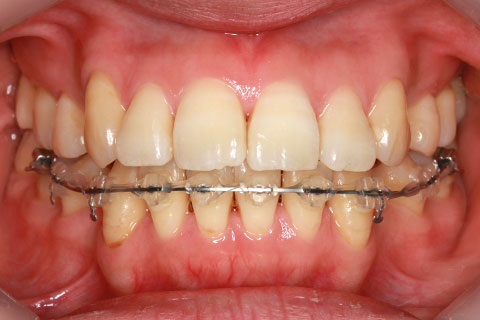

ハーフリンガル矯正3:上の歯のみ舌側矯正で治療(矯正期間24ヶ月)

治療中(開始直後)

- 年齢・性別

- 25歳女性

- 治療期間

- 2年0ヶ月

- 抜歯

- 上下4番抜歯

- 治療費

- 110万円

- 治療内容

- 施術の副作用(リスク)

- 表側矯正と比較して、力学的な操作性が複雑なため、ボーイングエフェクトを起こしやすい。